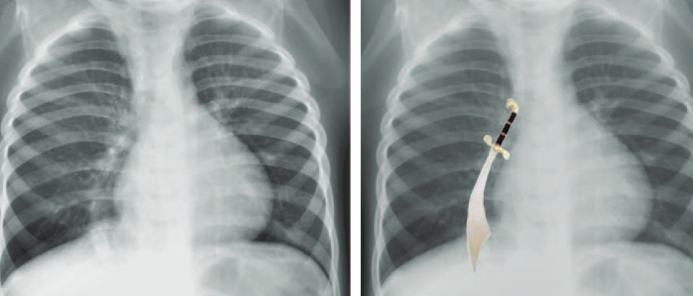

PAPVR

Partial Anomalous Pulmonary Venous Return

- Une ou toutes les veines pulmonaires DROITES se connecte hors de l’OG

- Signe du cimeterre

- Le Syndrome du Cimeterre se définit par:

- PAPVR

- Hypoplasie pulmonaire droite (pneumonies à répétition)